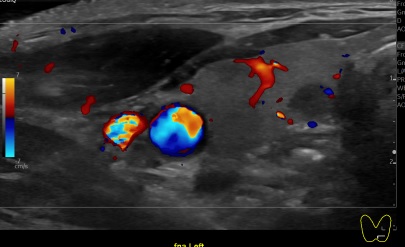

상기환자 외부검사이상소견 추적관찰위해  내원하신 60대 후반 여성분으로 갑상선 초음파 시행후 의심스러운 갑상선 좌엽 결절 세포검사 진행후 갑상선암으로 진단되었습니다